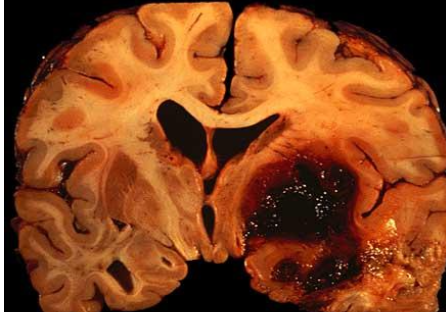

Hemorrhagic Stroke

▪ Caused by rupture or leakage of cerebral blood vessels.

▪ May be the result of weakness of a vessel wall or extreme fluctuations in blood pressure

1. Extracerebral hemorrhages-hemorrhages from blood vessels in the meninges or on the surface of the brain (bleeding outside brain).

2. Intracerebral hemorrhages-hemorrhages within brain or brainstem

Intracerebral Hemorrhage

Hemorrhage into the brain and brainstem (bleeding in brain tissues).

Most common sites are the thalamus and basal ganglia

Also possible: Brainstem (especially pons) and cerebellum

May be caused by aneurysm: pouch formed in weakened arterial walls

If aneurysm in cerebral artery bursts, severe aphasia is likely (big accumulation big burst)